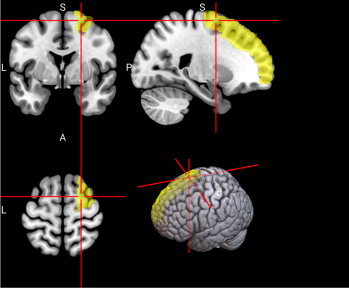

15,

16

L & R Supplementary motor area (SMA)

The SMA plays a role in self-initiated (voluntary) actions and is part of multiple voluntary motor loops [62].

/word/media/image11.png/word/media/image11.png